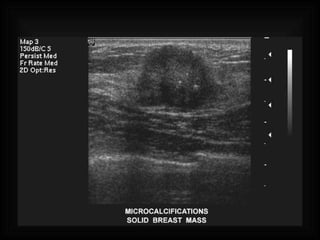

METODOS DE EXPLORACION AUTOEXPLORACION ULTRASONIDO MASTOGRAFIA

METODOS DE EXPLORACIONAUTOEXPLORACION ULTRASONIDO MASTOGRAFIA

BI-RADS ( BREAST IMAGING REPORTING AND DATA SYSTEM) I  NEGATIVO  no se observan imágenes sugestivas de cáncer II  HALLAZGOS BENIGNOS-NEGATIVO A CA. III HALLAZGOS PROBABLEMENTE BENIGNOS IV SOSPECHOSO DE ANORMALIDAD (biopsia) V  ALTAMENTE SUGESTIVO DE MALIGNIDAD

BI-RADS ( BREASTIMAGING REPORTING AND DATA SYSTEM) I NEGATIVO no se observan imágenes sugestivas de cáncer II HALLAZGOS BENIGNOS-NEGATIVO A CA. III HALLAZGOS PROBABLEMENTE BENIGNOS IV SOSPECHOSO DE ANORMALIDAD (biopsia) V ALTAMENTE SUGESTIVO DE MALIGNIDAD